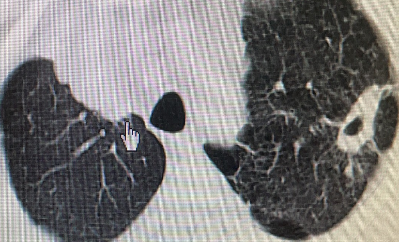

病理结果证实为肺腺癌,术后3个月复查CT:病灶已经逐渐吸收形成空洞了,就像在肺里留下了一道“烫伤疤痕”。

图片

治疗前dCJ帝国网站管理系统

射频消融后1天dCJ帝国网站管理系统

射频消融后2个月dCJ帝国网站管理系统